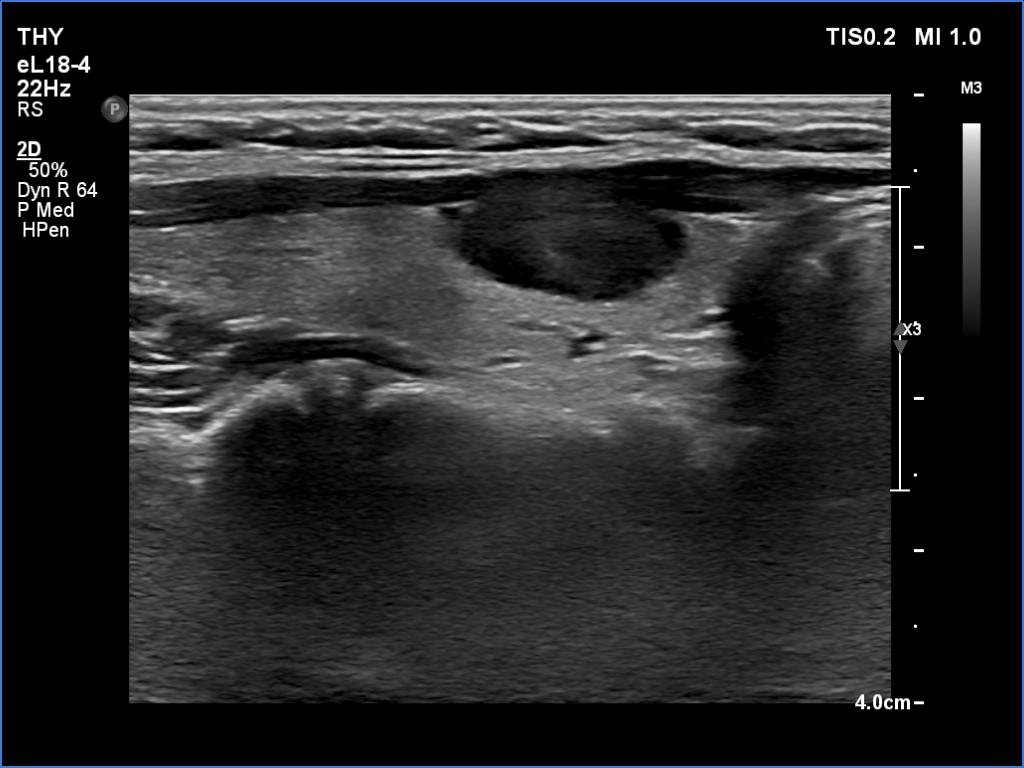

Ultrasonography. The thyroid was echonormal. There was a moderately hypoechoic nodule in the ventral part of the right lobe. This lesion has regular, sharp margins and presented signs of a possible extrathyroidal spread. The intranodular vascularity was increased. The left lobe had a tiny, minimally hypoechoic lesion. The largest diameter was 7 mm. The lesion had both echogenic lines and granules, a pattern corresponding either to connective tissue or back wall figure. The lesion had neither halo nor perinodular blood flow.

1. The nodule in the right lobe is remarkable because of the hypoechogenicity, the increased vascularity and because it shows sing of a possible extrathyroidal spread.